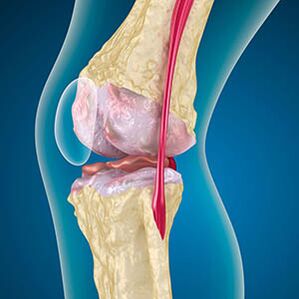

In the case of arthrosis, cartilage wear or completely missing the edges of the bones.Damaged tissue is not a source of pain because it has no receptor.In nearby structures, inflammation causes characteristic symptoms.

The body continues to regenerate damaged tissues, but the cartilage increases unevenly.As a result, irregularities develop that violate other elements of the joint.The nature of the osteophytes is explained by the compensation of the smooth joint cartilage.Another version indicates that the growth of "spurs"Due to muscle weakening, the joint is associated with a medial or lateral stabilization.

Swelling of soft tissues, inflammation of the tendons and joint bag.The appearance of heat in the knee, swelling indicates the accumulation of inflammatory secretions -Arthrosis is often accompanied by bursitis, synovites, tendinitis.

In the third stage of the jointThe pain becomes constant when bending and extending the joint.During the aggravation, the joint blushes and swells, and the painful pain does not stop at rest.Swelling around the knee appears, noticeable deformation of the joints of the joint.

- Uneven surfaces of the femur and tibia, loss of joint joints;

- Change in the form of patella;